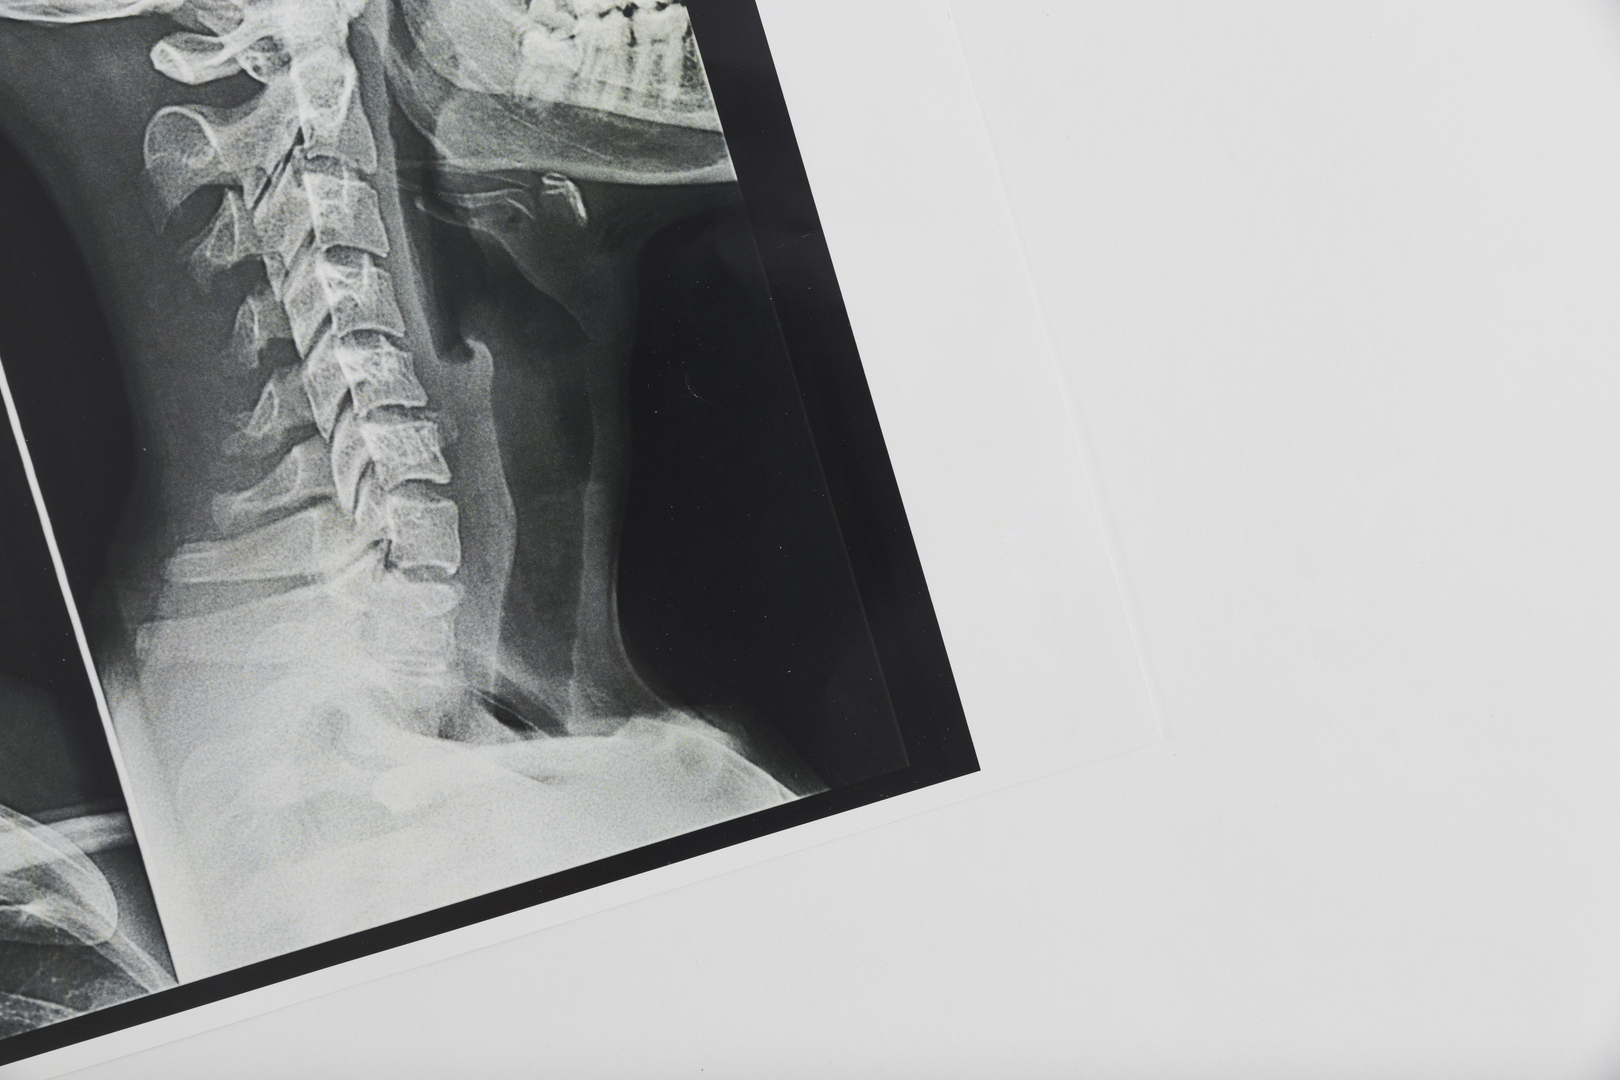

В Видном врачи спасли мужчину с «переломом висельника» после падения дома

Россиянин получил так называемый «перелом висельника» после того, как поскользнулся дома. Его экстренно прооперировали в больнице в Видном. Об этом сообщает Life.ru со ссылкой на Telegram-канал SHOT.